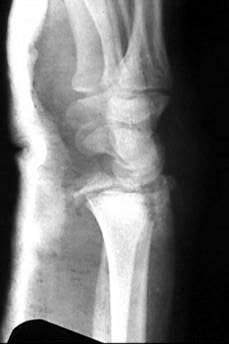

Больной из соседнего района 17 лет получил травму 8 09 03. Перелом по классификации E.Muller -В2

Неполный внутрисуставной перелом лучевой, тыльного края (Barton) Наложена гипсовая повязка рис 08 09. Через месяц на контрольной рентгенограмме найдено вывих л\з сустава. Рентгенограмма при обращении в нашу больницу 21 10 03 рис 21 10. На данные момент имеется умеренно выраженная контрактура, умеренные нейровегетативные нарушения.Обдумываем несколько вариантов лечения:1) Продолжить консервативное лечение и провести артродез, если останется болевой синдром.2) Провести открытую репозицию, устранить вывих, фиксировать отломок пластиной по тыльной поверхности.3) Провести артродез в лучезапястном суставе